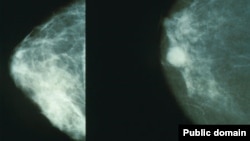

Дар Тоҷикистон, тибқи омори соли 2008-и Вазорати беҳдошт, 9634 нафар гирифтори саратон ба қайд гирифта шудаанд. Аз миёни онҳо 3900 нафар мард ва 5734 нафар зан мебошанд. Ҳамон сол сатҳи гирифторӣ ба саратон ба ҳар 100 ҳазор нафар 135,5 нафарро ташкил додааст. Соли 2009 суръати гирифторӣ ба саратон дар Тоҷикистон 11 дар сад афзоиш ёфтааст. Маъмултарин навъҳои саратон дар миёни шаҳрвандони Тоҷикистон саратони бачадон буда, дар навбати баъдӣ саратони пӯст, меъда ва шуш қарор доранд. Синни аксар гирифторони саратон 45-65-сола будааст.

Ива Татюнова, раҳбари Маркази протонии Ҷумҳурии Чех мегӯяд, дар миёни гирифторони саратон шумори зиёди мардон ҳам мебошанд, ки гирифтори саратони простата мешаванд. Маъмулан, баъди 45-солагӣ синни хатарнок барои мардон арзёбӣ шуда, машварат мешавад, ки ҳар сари чанд аз ташхиси табибон гузаранд. "Дар 97 дар сади ҳолатҳо муштариёни маркази мо, ки бо саратони простата муроҷиат мекунанд, аз ин дард комилан шифо ёфта, ба ҳаёти хушбахти худ бармегарданд. Таъсиси чунин як марказ дар Тоҷикистон, бовар дорем, ба фоидаи хонаводаҳои хеле зиёд мешавад, чунки ин беморӣ дар тамоми ҷаҳон дар ҳоли тавсеа мебошад", таъкид кард ӯ.

Мутахассисон мегӯянд, муолиҷаи саратон бахусус дар марҳилаҳои аввали гирифторӣ ба ин беморӣ хеле муҳим аст, вале дар Тоҷикистон на ҳама фарҳанги муроҷиати саривақтӣ ба духтур ва муоинаи тадриҷиро доранд. Дар Маркази протонии Ҷумҳури Чех мегӯянд, дар сурати ташкил шудани чунин як бунгоҳе дар Душанбе, расидагӣ ба беморони зиёде осон ва айни замон, камхарҷтар назар ба сафари онҳо ба хориҷа мешавад.